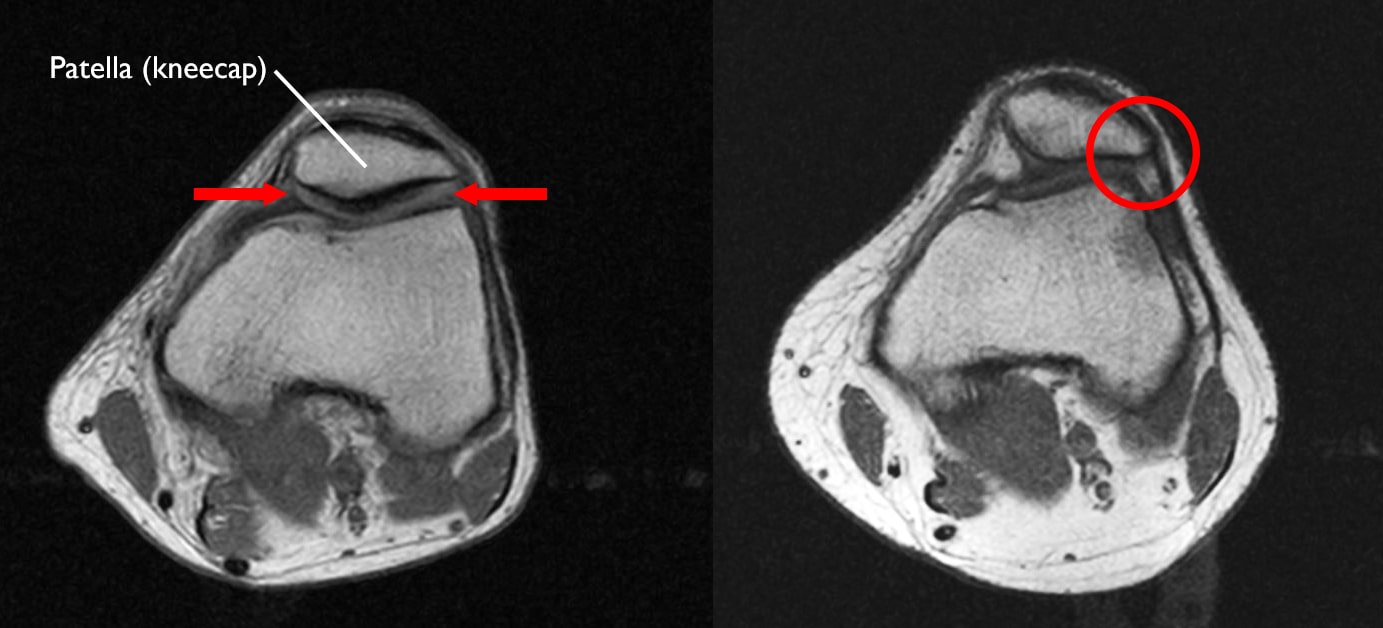

Runners knee is a broad term used to describe the pain you feel if you have one of several knee problems. The images show well-preserved medial and lateral compartments and severe arthritis in the patellofemoral compartment shown behind the patella kneecap at the end of the white arrow. Patellofemoral pain syndrome PFPS is the most common cause of knee pain in the outpatient setting.

A 22 Year Old Male Patient With Patellofemoral Pain Without Crepitation Download Scientific Diagram